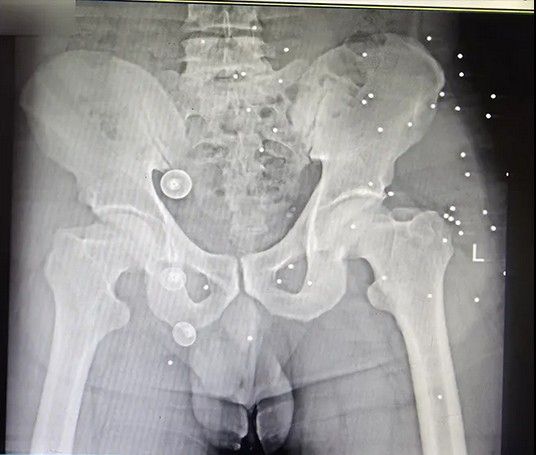

دست و پای معترضان در شهر رشت نیز از شلیکهای ماموران جمهوری اسلامی در امان نبودهاند. تصاویر رادیوگرافی نشان میدهد بسیاری از معترضان در ناحیه دست و پا هدف تیرهای ساچمهای قرار گرفتهاند، شدت آسیب در برخی موارد تا حدی بوده که استخوان ساعد، ساق یا مچ پا خرد شدهاند. همچنین موارد متعددی از شکستگی در دست و پای معترضان بدون شلیک گلوله نیز دیده میشود.

یکی از شدیدترین جراحات متعلق به زنی است که نه تنها کتف، بازو، ران و ناحیه تناسلی او هدف تیر ساچمهای قرار گرفته است، بلکه استخوان ران او نیز با اصابت گلوله جنگی خرد شده است. در تصاویر مشخص است که از فیکساتور برای درمان این مجروح استفاده شده است.

استخوانهای خردشده دست و پادست و پای معترضان در شهر رشت نیز از شلیکهای ماموران جمهوری اسلامی در امان نبودهاند. تصاویر رادیوگرافی نشان میدهد بسیاری از معترضان در ناحیه دست و پا هدف تیرهای ساچمهای قرار گرفتهاند، شدت آسیب در برخی موارد تا حدی بوده که استخوان ساعد، ساق یا مچ پا خرد شدهاند. همچنین موارد متعددی از شکستگی در دست و پای معترضان بدون شلیک گلوله نیز دیده میشود.